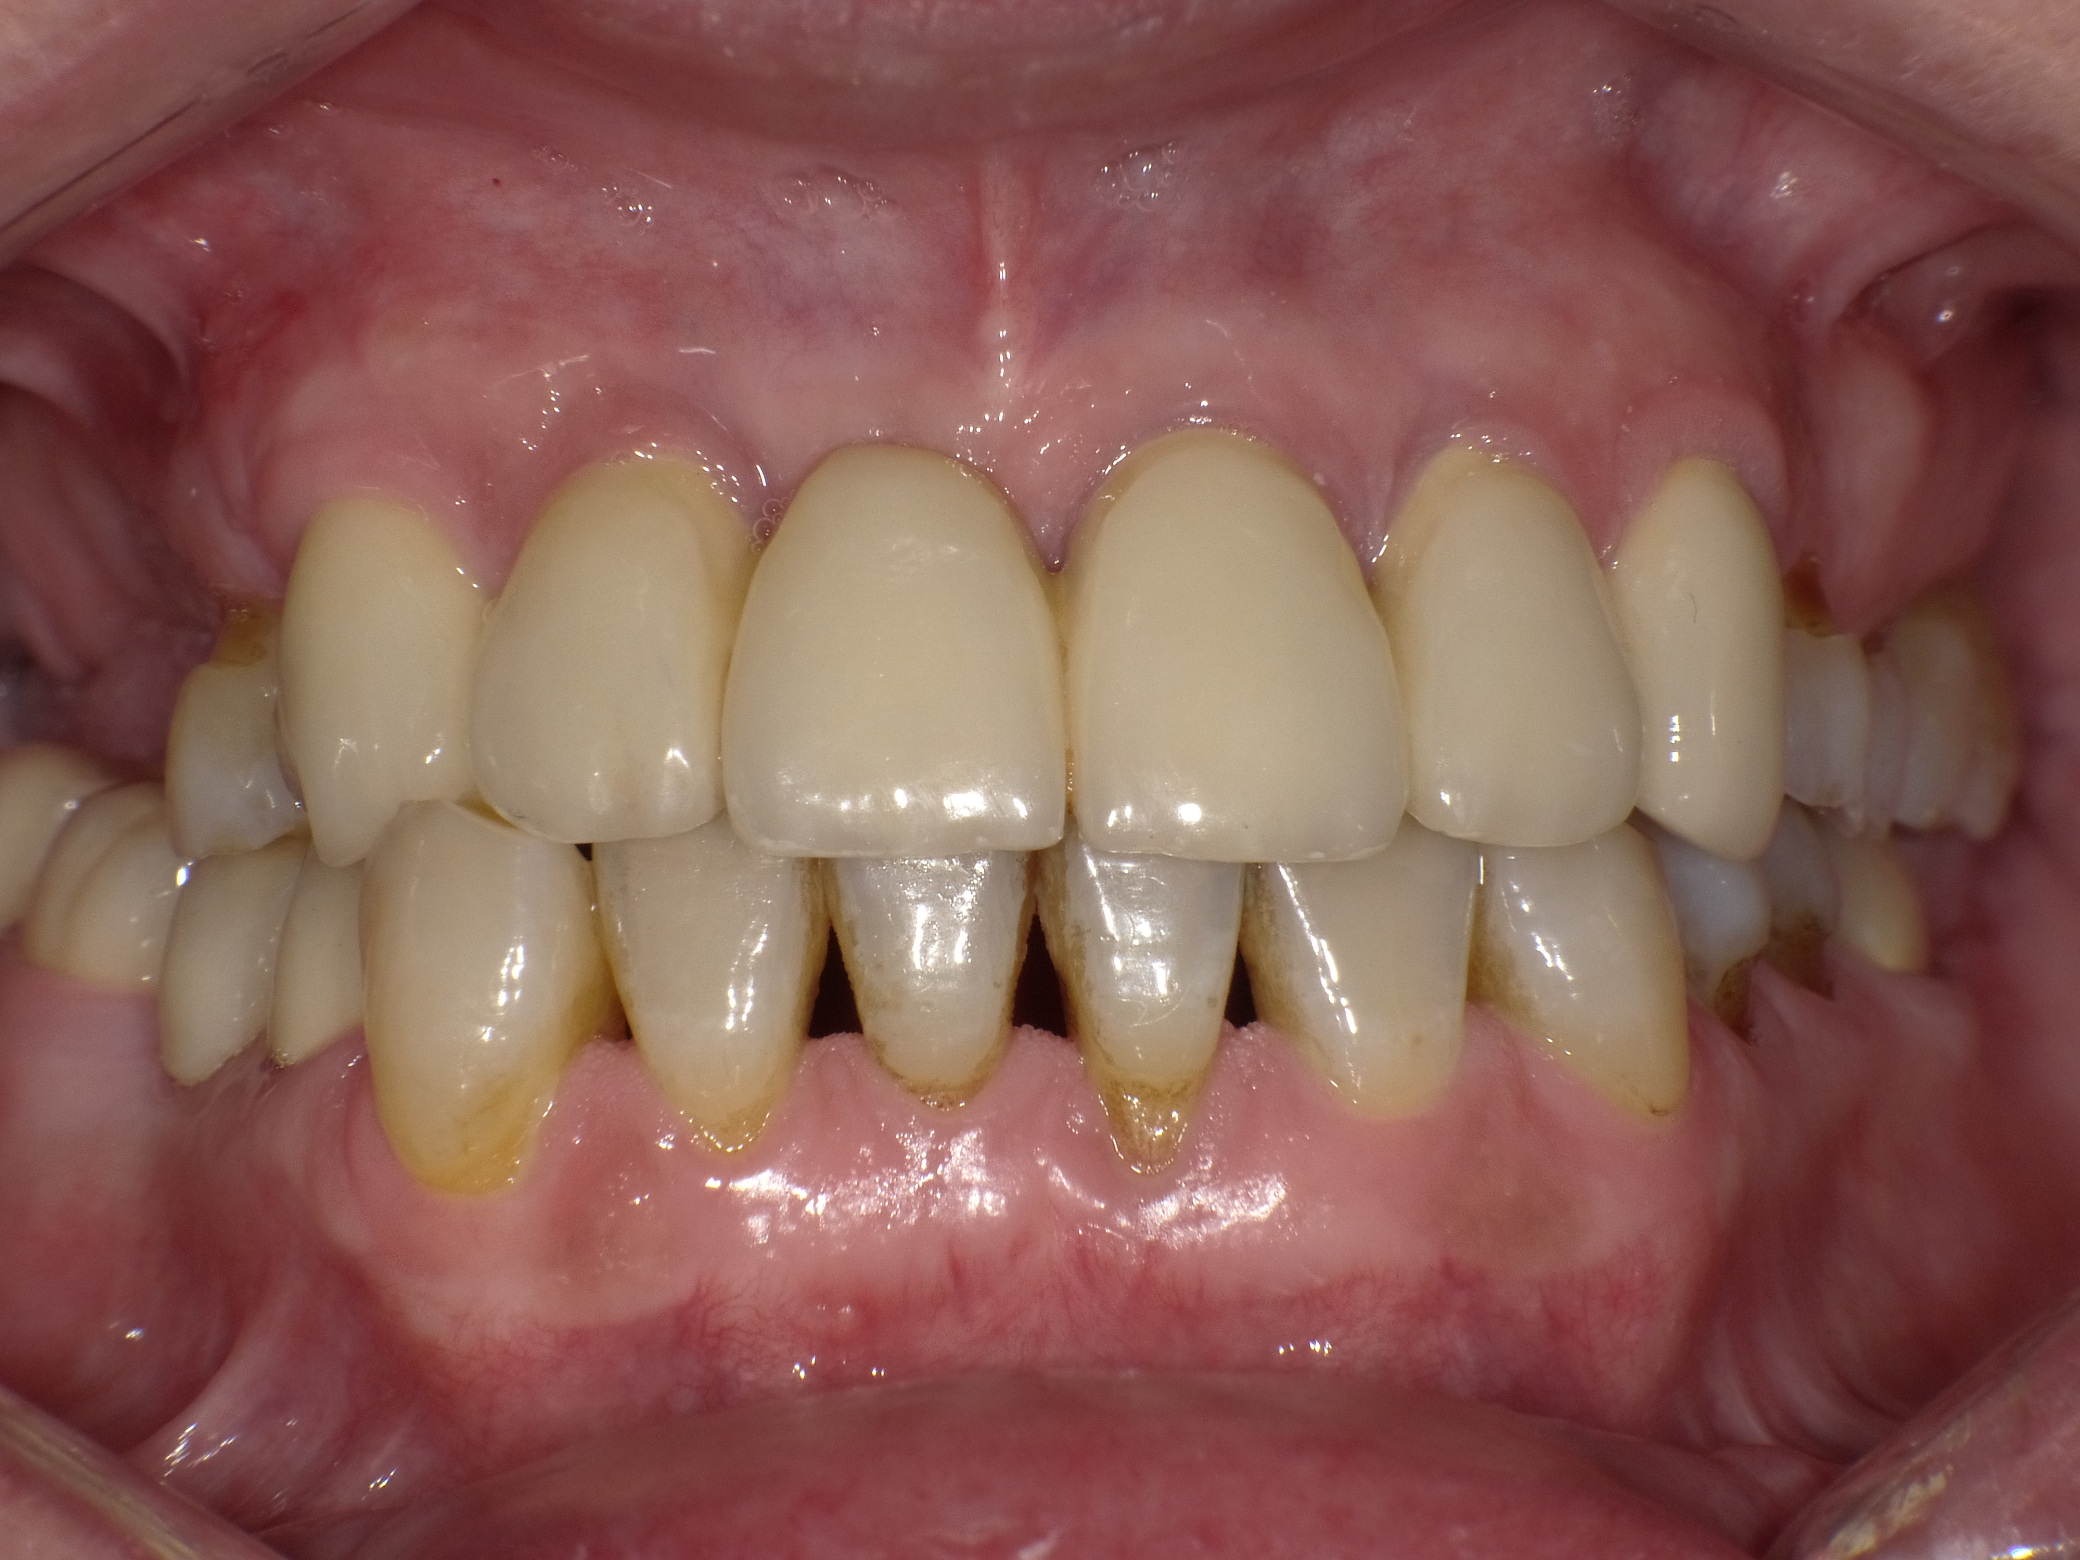

Unbefriedigende Ästhetik, vor allem aber Entzündungen im Knochen und eine massive Parodontitis mit bereits gelockerten Zähnen

Vorher: Unbefriedigende Ästhetik, vor allem aber Entzündungen im Knochen und eine massive Parodontitis mit bereits gelockerten Zähnen

Gesamtbehandlung in Sedierung: die Seitenzähne wurden durch Keramik-Implantate (Zahnentfernungen und Sofortimplantation) mit Knochenaufbau ersetzt; anschließend Gesamtüberkronung aus Vollkeramik mit Optimierung der Ästhetik

Nachher: Gesamtbehandlung in Sedierung: die Seitenzähne wurden durch Keramik-Implantate (Zahnentfernungen und Sofortimplantation) mit Knochenaufbau ersetzt; anschließend Gesamtüberkronung aus Vollkeramik mit Optimierung der Ästhetik